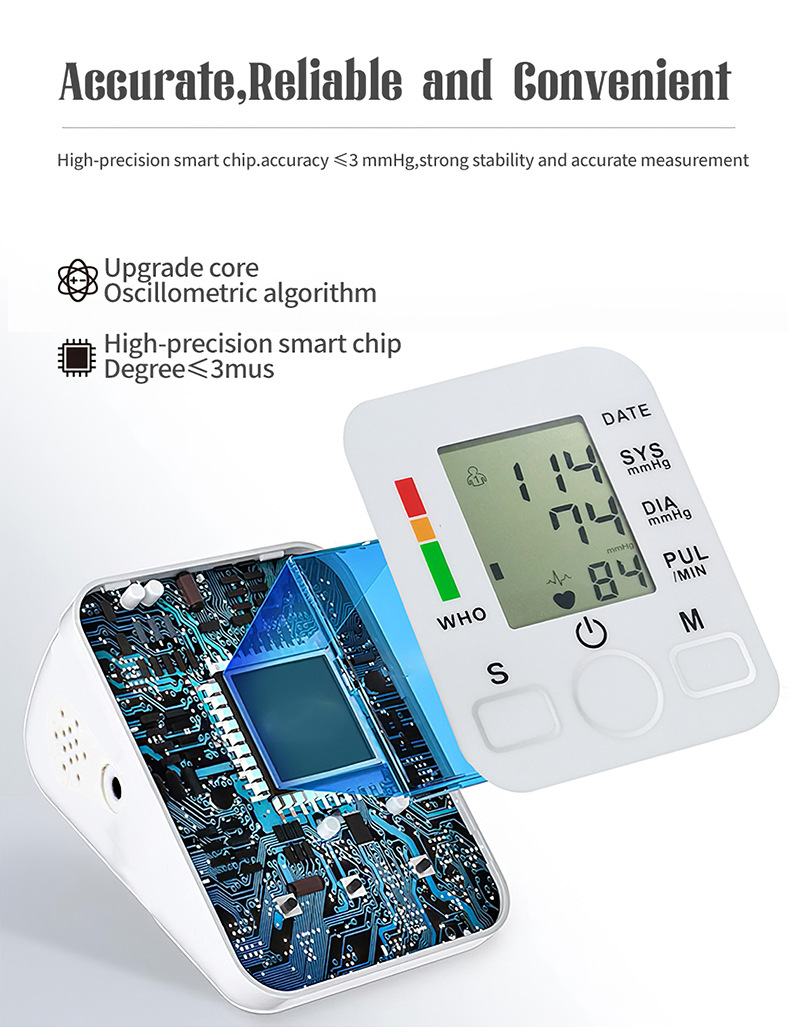

Product Image: